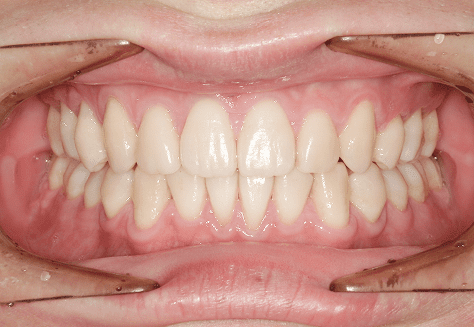

M.U

治療前

治療後

主訴

下の歯が特にガタガタなのが気になる。上の前歯が1本反対になっている。

診断

下顎前突・叢生・反対咬合

年齢/性別

20代/男性

抜歯部位

非抜歯

使用装置

上下インビザライン(PBM使用)

保定装置

ビベラリテーナー

診察料金

5,500円×16回

治療期間

1年7カ月